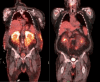

VEXAS syndrome (vacuoles, E1 enzyme, X-linked, autoinflammatory, somatic) is an increasingly recognized disorder that occurs due to somatic mutations of a ubiquitin-activating enzyme encoded by ubiquitin-like modifier activating enzyme 1 gene, UBA1. Clinical findings associated with VEXAS syndrome include recurrent fevers, polychondritis, periorbital edema, pleural effusions, myocarditis and/or pericarditis, hepatosplenomegaly, myelodysplastic syndrome, cytopenias, inflammatory arthritis, neutrophilic dermatosis, and deep venous thrombosis. Novel renal manifestations like interstitial nephritis are infrequent, and to our knowledge, acute renal failure due to C3 glomerulonephritis (C3GN) has not yet been reported. Overwhelming systemic inflammation can result in morbid end-organ damage and death. While there is no formal guideline or established protocol for its management, treatment of VEXAS syndrome with tocilizumab, an interleukin-6 (IL-6)-directed therapy, has been described in the literature. Here, we report a case of a 71-year-old male patient presenting with C3GN as an initial manifestation of VEXAS syndrome and explore the rationale for our approach to treatment with IL-6 blockade. Our patient was initially treated with two inpatient doses of tocilizumab with successful transition to siltuximab in the outpatient setting. He continues to benefit from ongoing siltuximab treatment for more than one year to date without any safety issues or relapse of VEXAS syndrome.

Figures